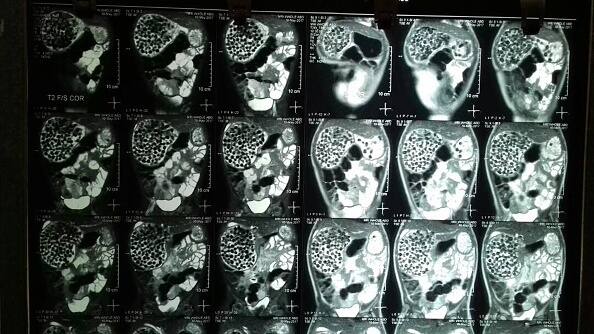

OMG! एक्स-रे में इस आदमी के पेट से दिखे पत्थर, सिक्के और बोतल के ढक्कन, जानें फिर क्या हुआ

इस ऑपरेशन के तहत जियांग की एंडोस्कॉपी और गैस्ट्रोकॉपी भी हुई.